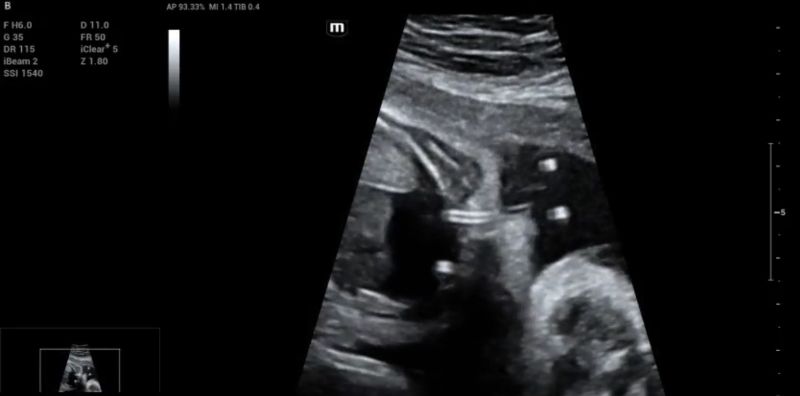

Additionally, a wide muscular ventricular septal defect (VSD) (Fig 2). and agenesis of the ductus venosus with extrahepatic drainage to the inferior vena cava (Fig 3). were diagnosed.

3D color reconstruction of the abnormal ductus venosus drainage into the inferior vena cava (white arrow)

Figure 3: 3D color reconstruction of the abnormal ductus venosus drainage into the inferior vena cava (white arrow).